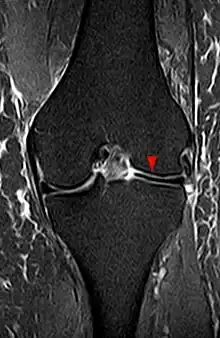

The transverse diameter of a normal meniscus is approximately 10 to 11 mm; therefore a normal meniscus body will be visible on only 2 slices of a MR with 4-5-mm sagittal slices. A discoid meniscus should be considered if more than two contiguous body segments are present. However, this method may lead to a false negative when evaluating people with the Wrisberg variant of discoid meniscus since it maintains a narrow crescent shape. Coronal and radial images of the meniscus are useful to demonstrate the extension of the aberrant meniscus into the joint as seen here. On coronal images, it is diagnosed when the horizontal measurement between the free margin and the periphery of the body is more than 1.4 cm.[2] Rarely, X-ray may show lateral joint space widening, squaring of the lateral condyle, cupping of the lateral tibial plateau and hypoplasia of the lateral tibial spine that suggest discoid meniscus.